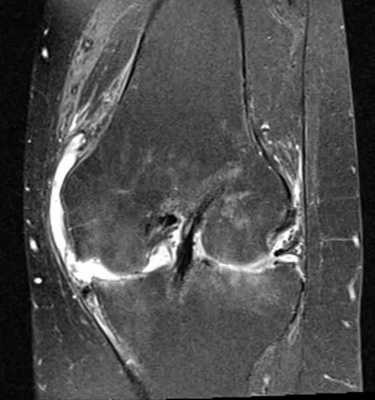

МРТ коленного сустава в прямой проекции. Определяется избыточное наличие синовиальной жидкости (яркий сигнал) на фоне разрушения мениска и нарушения конгруэнтности костей и их деформации.

МР-снимок коленного сустава в режиме Т2, контузия кости